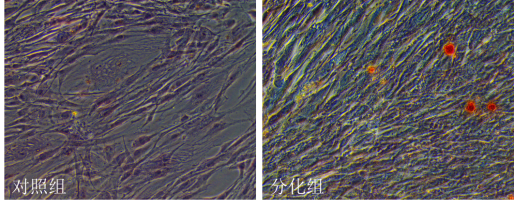

二、 hMSCs成脂細胞誘導分化:

hMSCs在相關誘導分化培養基培養14~28 d后,經油紅O(oil red 0)染色為陽性,根據脂肪組織細胞的特點:細胞漿中含有脂肪滴,可以通過油紅O對細胞中脂肪滴染色。說明分化的細胞內形成脂滴。

油紅O(蘇丹紅)是一種脂溶性偶氮染料,能特異性地使組織和細胞內中性甘油三脂、脂質以及脂蛋白等染色。油紅 O 配成染色液用于染色時,可以通過相似相溶的原理使組織或細胞內的脂滴著紅色,可用于分析組織或細胞樣本中的脂質分布情況。